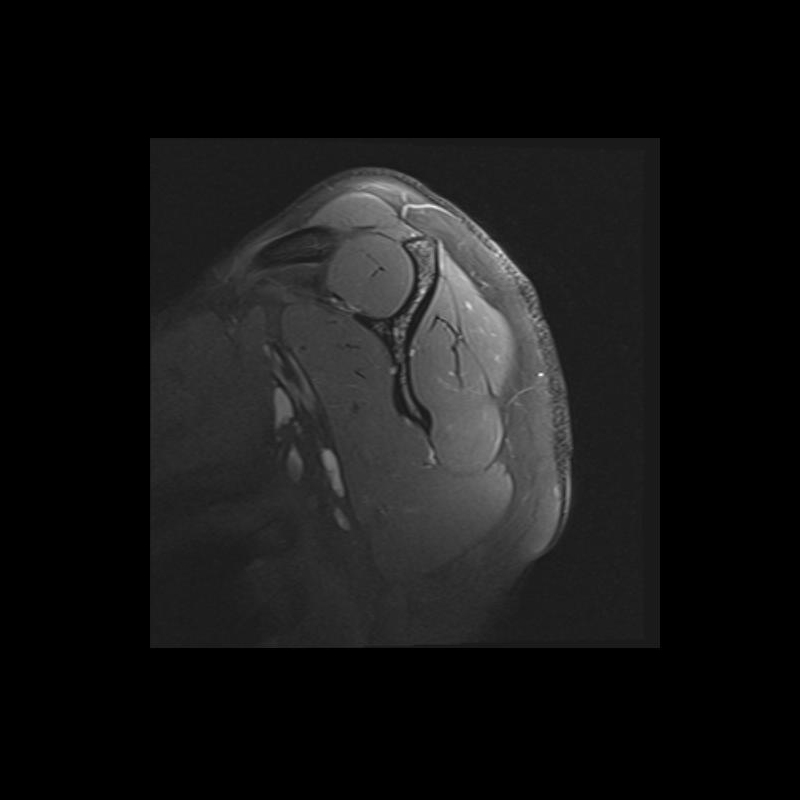

Shoulder MRI Anatomy